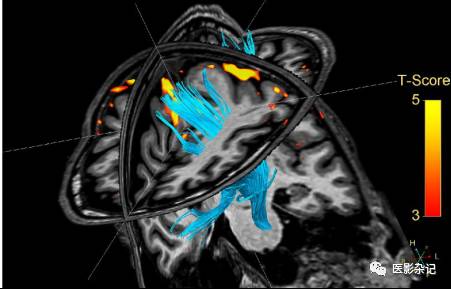

此外,由于对复杂疾病的诊断往往需要综合查看多种不同方式扫描序列,所以,对不同序列的配准及融合显示功能也非常有价值。包括不同参数图像之间、参数图像与解剖形态图像之间的配准与融合。例如,下图显示的将功能图像融合显示在形态图像上。

*来自GE BrainWave

在下面这个更复杂的例子中,将三种扫描序列进行了融合显示,包括灰度显示的反映解剖形态信息的T1序列;以橙色高亮区域“贴”在灰度图上显示的fMRI活跃区域,反映了大脑当前的功能活跃区域;以浅蓝色三维纤维束立体显示的DTI影像,反映了白质纤维束在颅内的走行。

*来自Philips

*来自Philips

在颅脑MRI影像查看与分析领域,GE公司推出 BrainView 和 BrainWave 两项专科软件系统。其中,BrainView能够支持对DWI、PWI、DTI及fMRI等序列的查看,并且集成了伪彩显示、配准、融合等功能。BrainWave则专注于fMRI的查看与分析。Philips公司IntelliSpace影像系统、Siemens公司Sygo.MR中也提供了对应DWI、PWI、DTI、fMRI扫描序列、并且与颅脑疾病诊断相关联的影像查看与分析功能模块。